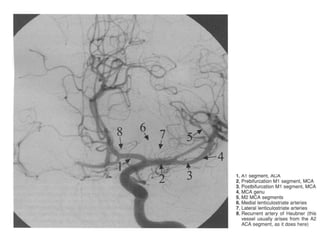

Segmentação da ACA

• A1 (pré-comunicante): . acima do quiasma óptico até unir-se

a AComA. A hipoplasia desse segmento correlacionasse

com a formação de aneurismas.

• A2 (infracaloso): começa na AcomA, dirige à lamina

terminal e termina na junção do rostro do corpo caloso.

• A3 (pré-caloso): se estende em torno do joelho e termina

onde a artéria se curva abruptamente para sentindo

porterior.

• A4 (supracoloso): porção anterior do segmento horizontal

• A5 (caloso posterior): porção posterior do segmento

horizontal

Artéria recorrente de Heubner

• Curva-se na direção oposta a sua origem, passando acima da

bifurcação da ACI e da ACM na parte medial do sulco lateral.

• Geralmente oriundo do segmento distal de A1 ou da porção

proximal de A2 ( mais comumente de A2).

• Em seu trajeto está intimamente relacionada à porção superior ou

posterior de A1.

• Pode entrar na SPA como um único tronco ou se ramificar.

• Irriga a porção anterior do núcleo caudado, o termo anterior do

puramente, fascículo uncinado, parte âóntero-inferior do braço

anterior da cápsula interna.